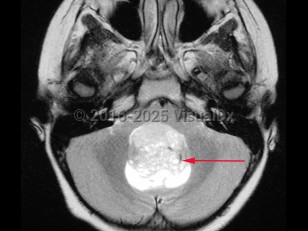

Medulloblastoma in Adult

A medulloblastoma is a malignant primary brain tumor located in the posterior fossa near the fourth ventricle. It is the most common malignant brain tumor in children. One-third of cases present in children aged younger than 3 years. In adults, the tumor usually presents before age 40.

Initial symptoms may relate to increased intracranial pressure as a consequence of blockage of the fourth ventricle, causing morning headache, nausea / vomiting, and irritability. Later, patients can develop ataxia, frequent falls, papilledema, diplopia, nystagmus, and/or neck stiffness.

This tumor may spread through the cerebrospinal fluid (CSF) to other parts of the brain and spinal cord. It is an aggressive tumor and recurrence is common. Five-year survival rates are about 60% in all age groups. Patients with medulloblastoma are considered higher risk if they present as infants or at an older age, have metastatic disease, and if their tumors have aggressive histopathology or specific molecular markers.